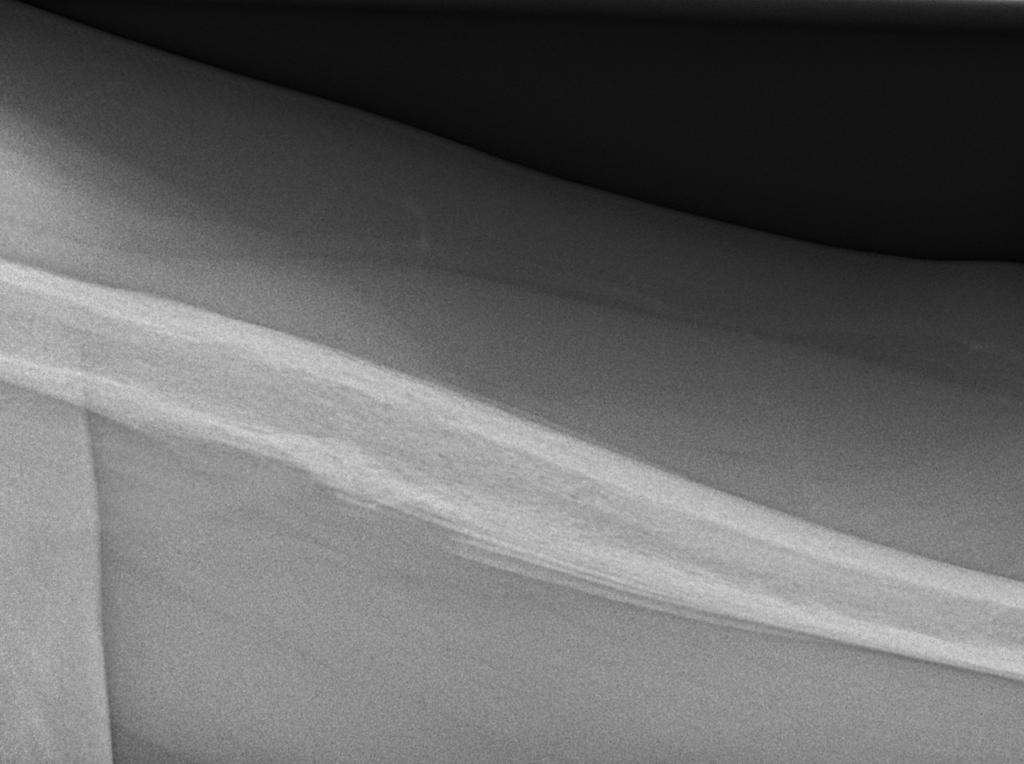

Imaging features of Ewings sarcoma

1. Typically occurs in children and adolescents between 10-20 years of age (95% between 4-25 years of age).

2. It is the 2nd most common malignant primary bone tumours of childhood after osteosarcoma, typically arising from the medullary cavity.

3. Present as moth-eaten, destructive, and permeative lucent lesions in the shaft of long bones, with a large soft tissue component and typical onion skin/lamellated periostitis. These tumours may also involve flat bones and can appear sclerotic in up to 30% of cases.

4. Seen in long bones (femur > tibia> humerus), more than flat bones (pelvis, scapula, ribs)